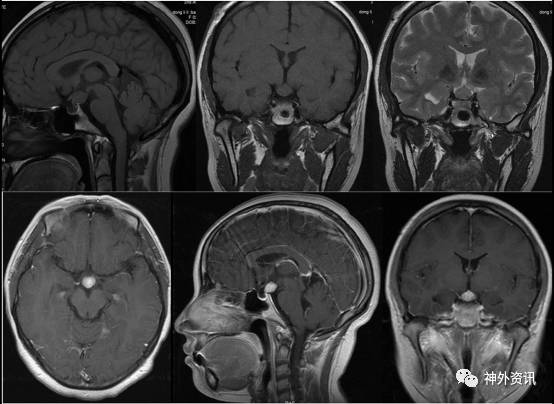

Covington ME等10报道部分病患特定的影像学表现(图6)可使神经影像学医师术前诊断垂体细胞瘤。虽然少数垂体细胞瘤以这种方式在影像学上表现,但如果影像显示肿瘤完全在鞍内,并与腺垂体分界清晰,垂体细胞瘤诊断可能性较大。这样的影像学特征在 SCO 或 GCT 的病例中未见类似表现。同样在垂体腺瘤、淋巴细胞性垂体炎或生理性垂体增生的病例中也十分罕见。

图6. 垂体细胞瘤影像学表现。鞍区 MRI 矢状位(A)和冠状位(B)示鞍上一圆形占位,增强均匀,与正常腺垂体分界清晰。

本病例中影像学显示肿瘤考虑垂体柄或神经垂体来源,与腺垂体分界清晰,与 Covington ME 等人报道的垂体细胞瘤的影像学特征性表现相符合。

Covington ME 等10认为对于 SCO 的病例影像学上通常表现为合并鞍内和鞍上病变(图 7)。因此一个完全位于鞍内或鞍上的肿瘤是 SCO 的可能性较小。SCO 起源于腺垂体,而垂体细胞瘤和 GCT 起源于神经垂体。因此如果影像学显示肿瘤位于或起源于神经垂体,那么 SCO 的诊断可基本排除。此外,SCO 表现为浸润性生长,与垂体分界不清,因此仅靠影像学表现难以与常见的鞍区病变如垂体腺瘤或淋巴细胞性垂体炎鉴别诊断。

图7. 梭形细胞嗜酸细胞瘤(SCO)影像学表现。鞍区 MRI 冠状位 T1 像(A)和冠状位 T2 像(B)显示鞍内和鞍上一浸润性生长的肿物。矢状位 T1 像(C)示被肿瘤浸润性生长后增大的垂体前叶,以及肿瘤未侵犯的神经垂体的移位。

本病例中影像学显示肿瘤起源于神经垂体,且内分泌检查无全垂体功能减退表现,因此术前可排除诊断 SCO 的可能性。

GCT是一类起源于神经垂体和(或)垂体柄的罕见肿瘤。Covington ME等10报道显示 GCT 在增强 CT 上通常强化明显,在 MRI 中 T1、T2 像呈等信号,均匀或混杂强化。大部分 GCT 主要位于鞍上,几乎没有 GCT 完全位于鞍内。因此单纯鞍内病变不考虑诊断 GCT。周刊第七期(点击查看)曾报道一例鞍上颗粒细胞瘤病例,头颅 MRI 显示肿瘤位于鞍背上方,与垂体分界清晰,强化明显但欠均匀,边界尚清(图 8)。

图8. 本周刊第七期报道的一例颗粒细胞瘤的 MRI 影像。可见鞍上占位,呈等 T1 弛豫信号,T2 呈混杂低信号,增强明显但不均匀,界清,与垂体分界清晰。

本病例影像学中虽然肿瘤完全位于鞍上,但术前 CT 示肿瘤呈等密度,未见高密度结节影,故与 GCT 的影像学表现不符。综上所述,术前根据影像学和临床症状表现,应首先考虑垂体细胞瘤可能,术后病理也证实了该诊断。